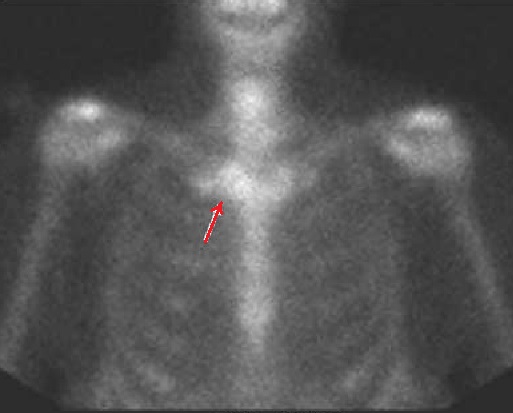

La captation focale du subtance radioactif sur la

scintigraphie osseuse se donne image de « tête de taureau

» de articulation sterno-clavicul;aire droit ( fleche rouge

) d'une hyperostose

sterno-costo-claviculaire (SCCH) |